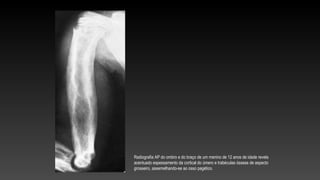

Radiografia AP do ombro e do braço de um menino de 12 anos de idade revela

acentuado espessamento da cortical do úmero e trabéculas ósseas de aspecto

grosseiro, assemelhando-se ao osso pagético.